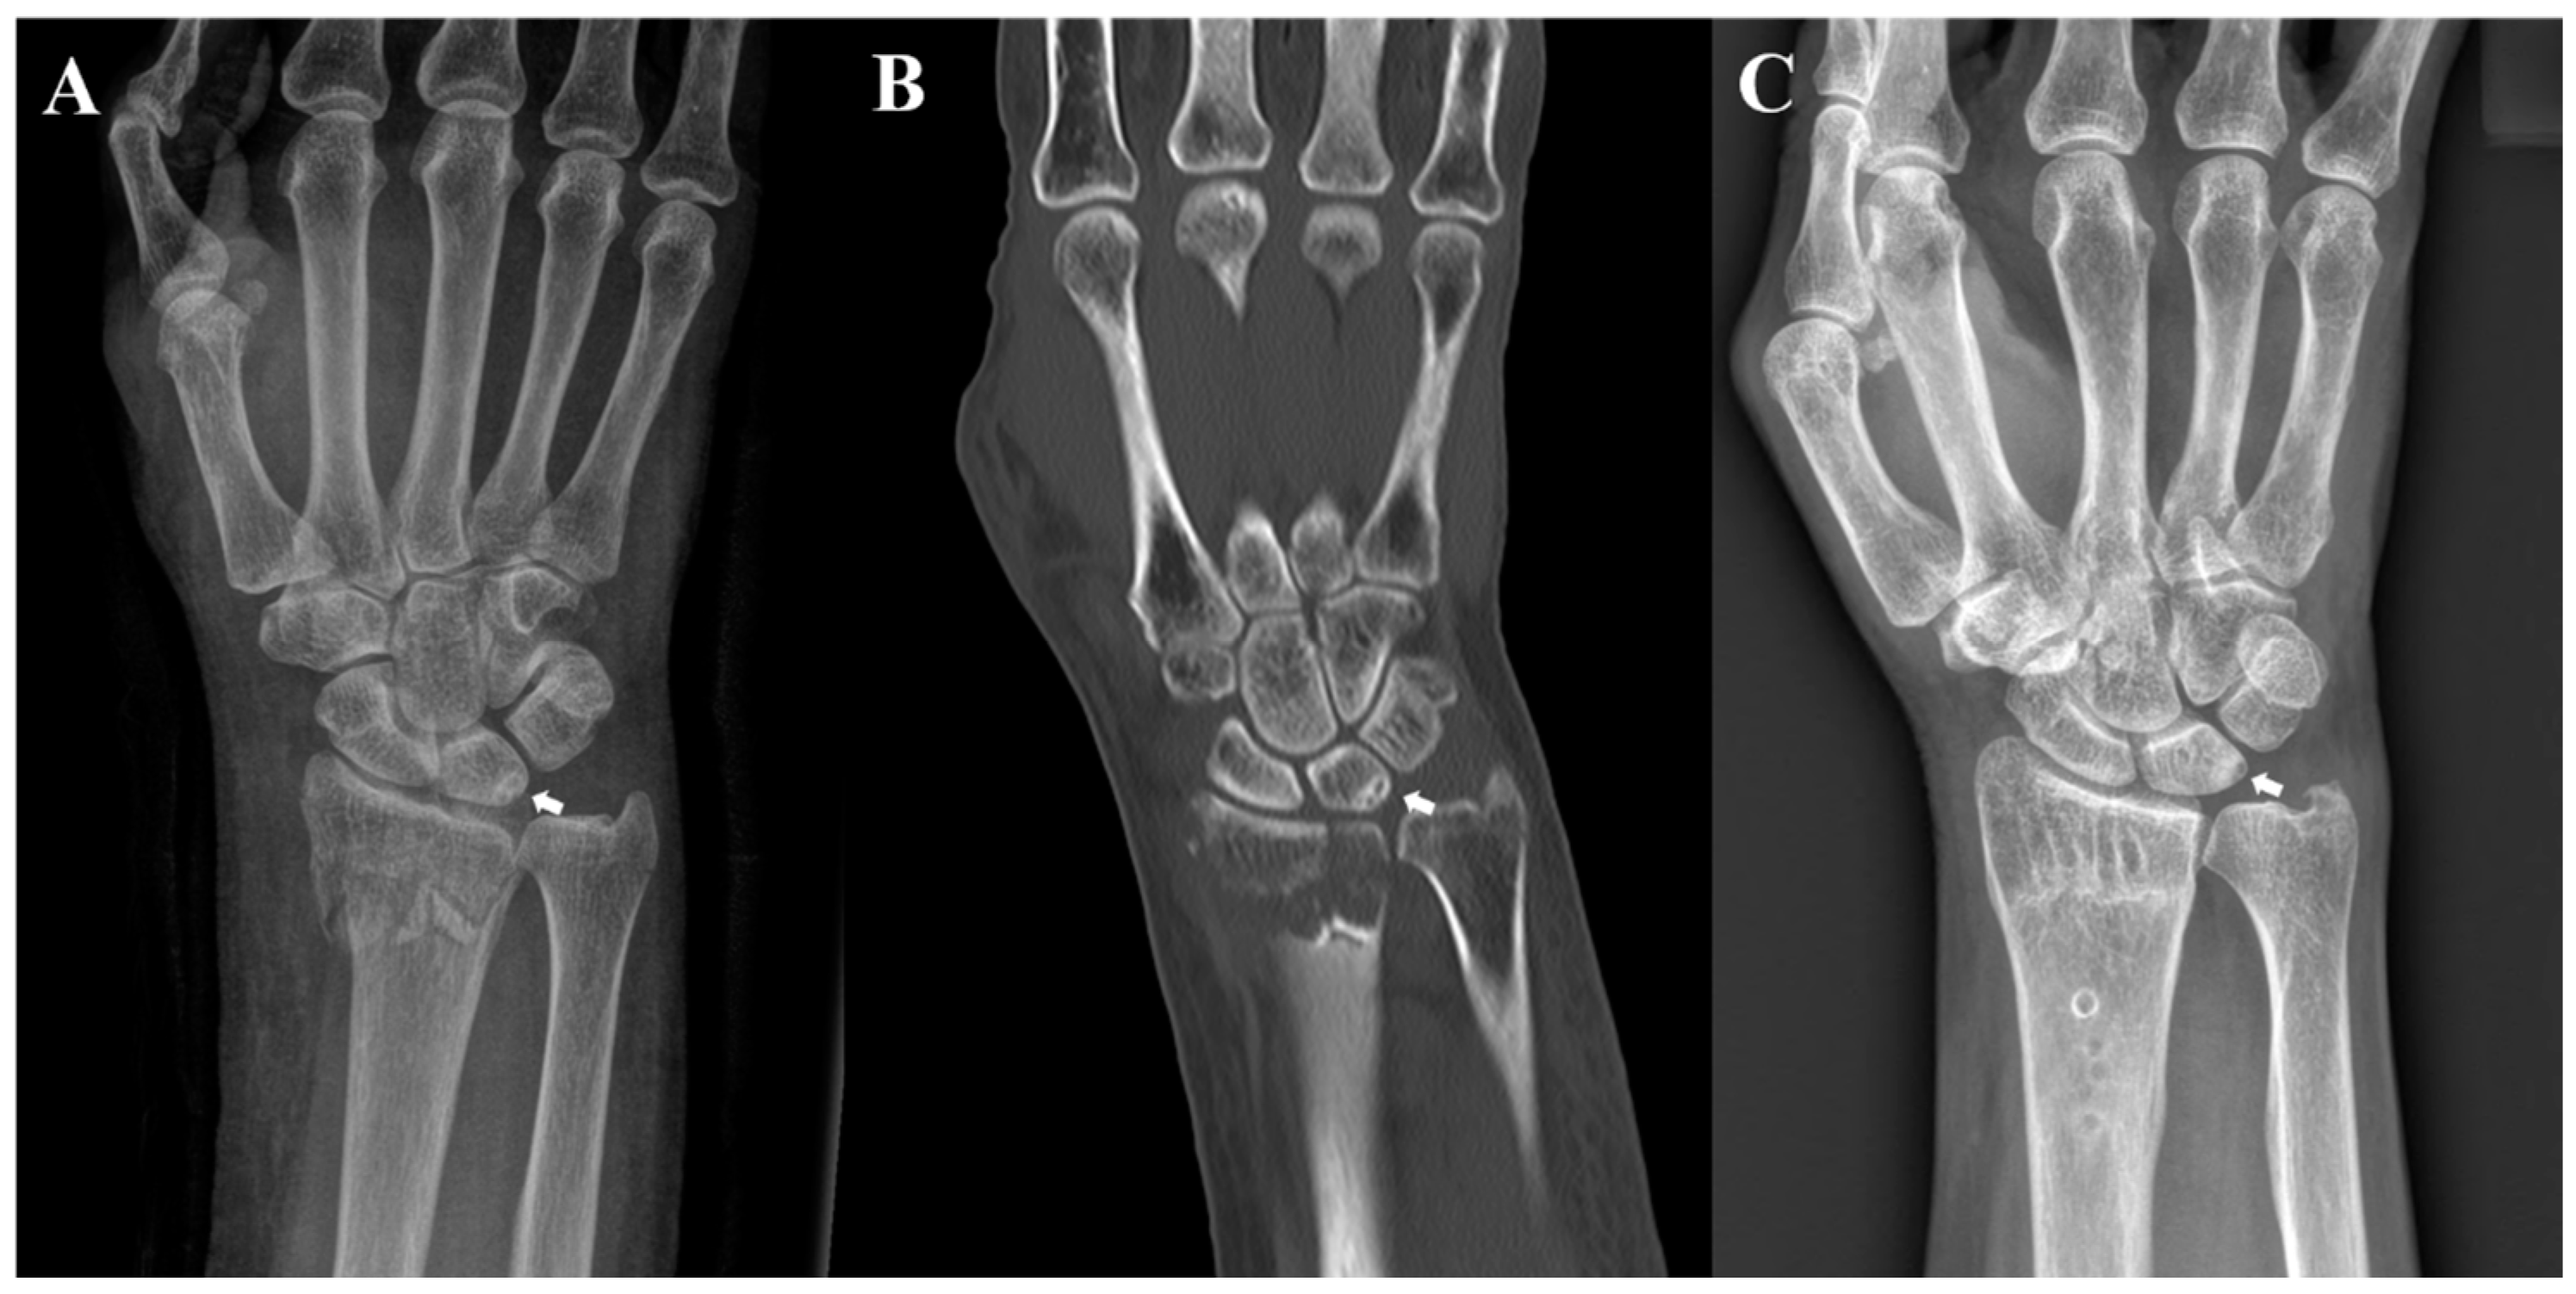

Patients who underwent open reduction and internal fixation for DRF between July 2015 and December 2020 were retrospectively analyzed. During this period, 432 underwent VLPF for DRF. Among them, 63 were excluded due to meeting the following exclusion criteria: history of carpal bone fracture (n = 6), Kienböck’s disease (n = 1), or inflammatory arthritis (n = 6); presence of ipsilateral upper-extremity fractures including distal ulnar and shaft fractures, except ulnar styloid process fractures (n = 12), or presence of open fractures (n = 2); and inadequate radiographs for obtaining a true measurement (n = 20). Patients who were not monitored for more than 12 months were also excluded (n = 16). Finally, 369 patients were included in this study. Of them, 18 with subchondral sclerosis with or without cystic changes in the proximal ulnar portion of the lunate identified on preoperative plain radiographs and CT scans were included in Group A (Figure 1A–C). To uniformly match the age, sex, and fracture pattern with a standardized difference of <0.1, 72 patients from among the remaining 351 patients were included in Group B, which was the control group subjected to 1:4 cohort matching using nearest neighbor matching (propensity score matching) (Figure 2) (Table 1). This study was approved by our hospital’s Institutional Review Board (KHNMC 2021-02-012), which waived the requirement for informed consent. All patients’ data were made anonymous and kept confidential. All procedures were indicated and performed in compliance with our department’s standards and the Declaration of Helsinki.

Figure 1.

Radiographs of a 70-year-old woman. (A) Preoperative posteroanterior radiograph and (B) coronal computed tomography image revealing sclerosis with cystic changes on the ulnar side of the lunate; (C) posteroanterior radiograph acquired after the removal of internal fixation at 12 months after surgery reveals the remnant sclerotic lesion with cystic change of the lunate.